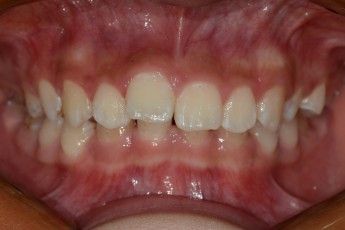

Before

After